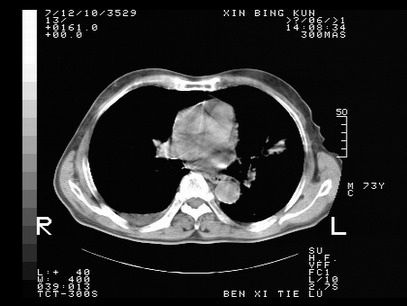

标题: CT10820:男,73岁,病史肺TB,现病史肺炎,直肠CA术后 [打印本页]

标题: CT10820:男,73岁,病史肺TB,现病史肺炎,直肠CA术后

双肺间质改变,依据病史双肺多发结节灶考虑转移,少量胸水.

1.两肺结核.2.两肺多发转移瘤.3右侧少量胸腔积液4.主动脉钙化.

双肺多发结节及条片状致密影,右侧少量胸腔积液。临床:直肠ca术后,肺tb病史。综合考虑:1 双肺转移!2 继发性肺结核合并感染!

此人病史较复杂,原有肺结核,直肠癌术后。肺部病灶形态亦呈多形性。因此,不可仅以一种病来解释肺部的病变。双肺多发的类圆形结节灶,结合病史还是首先考虑转移瘤,而双肺其余病灶还需结合化验室检查,结核或肺部感染在无其它检查资料的情况下不好排除。还是那句话----放射科医生不是开照像馆的,我们也是医生,看片一定要多结合临床及其它检查资料。要当一名合格的放射科医生,并不比当一名临床医生容易,我们可别把自已不当医生看。

两肺多发结节影,并见滋养动脉与其相连,考虑 两肺转移. 右侧胸腔积液考虑胸膜转移.

左肺上叶下叶背段,右肺中下叶见多发斑片状、条索状高密度影,兵变周围小结节影形成“树芽”样改变。 左肺上叶舌段近前胸壁处及右肺中叶内侧段见结节影。右侧胸膜腔内见液体密度区。纵隔内未见明确增大淋巴结。考虑左肺上叶舌段近前胸壁处及右肺中叶转移瘤可能性大。两肺继发型肺结核。右侧胸腔积液。

还有心包少量积液。